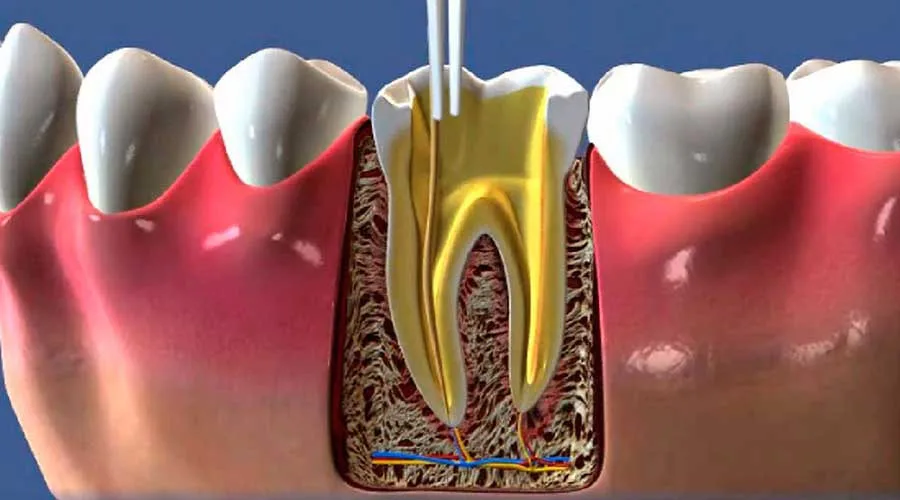

Recursos Técnicos: Uso de tecnologias de diagnóstico por imagem e métodos de desinfecção profunda;

Procedimento Curativo: Limpeza, drenagem (se necessário) e uso de materiais biocompatíveis sob rigorosa biossegurança;